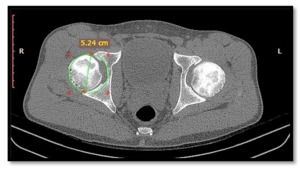

On CT with MPR images, circular designs encompassing the entire acetabulum are created at the position with the largest dimensions to measure the diameter of the acetabular opening (Image 1). On coronal images, the depth of the acetabulum is measured as the distance between the deepest point of the acetabulum and the line connecting the “tear drop” to the outermost point of the acetabulum (Image 2). The acetabular depth ratio is calculated as the depth of the acetabulum divided by the length of the line connecting the “tear drop” to the outermost point of the acetabulum, multiplied by 1000.